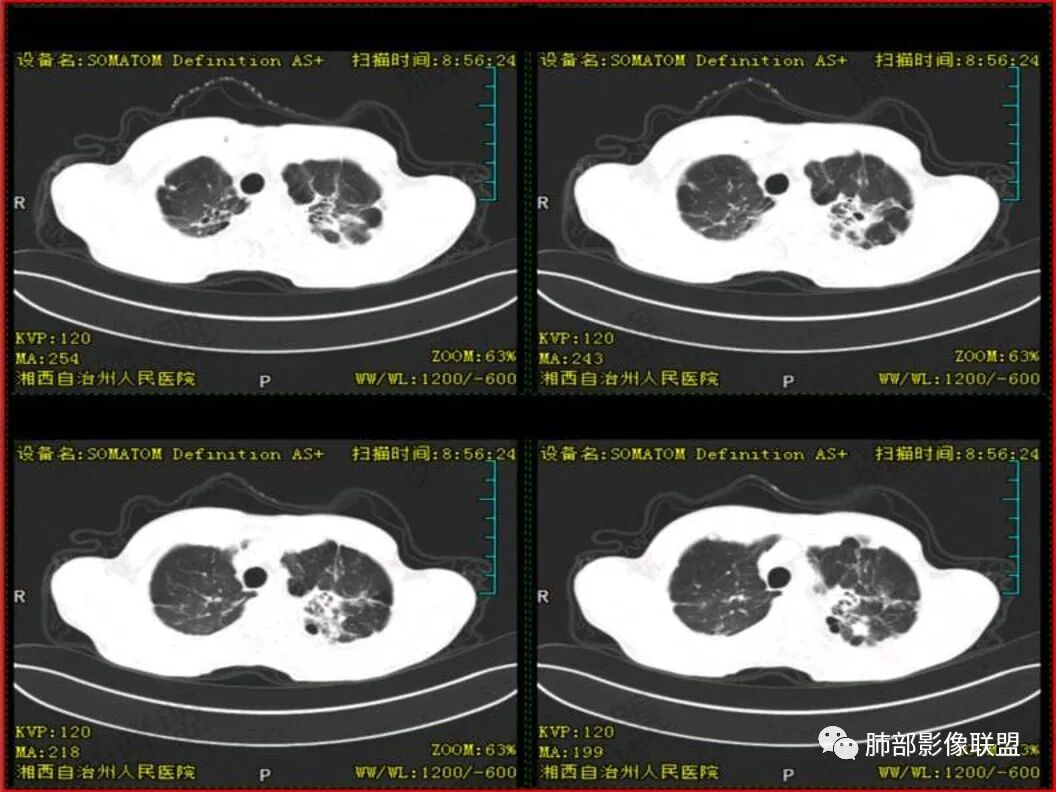

患者中年男性,以咳嗽 胸痛就诊

既往有肺结核病史

胸CT可见右肺下叶前基底段占位性病变,病灶周围可见周围不清毛玻璃影,病灶边缘可见分叶,呈膨胀性生长,纵隔窗可见病灶内呈偏心性坏死,增强扫描静脉期强于动脉期,纵隔隆突下淋巴结可见肿大坏死。

双肺肺气肿伴纤维索条,结节影,以双上肺为主,部分可见支气管扩张,右肺下叶实性肿块,边缘毛糙,病灶较密实,支气管堵塞可能?平扫密度尚可,增强后不均匀强化,叶裂可见多个结节影,纵隔淋巴结肿大,考虑:肺癌伴陈旧性肺结核,肺脓肿伴陈旧性结核

老年男性,既往有肺结核病史。影像双上肺病灶考虑陈旧性肺结核病灶,关键是右下肺团块影,从视频看,右下叶前段分支有堵塞,病灶局部膨隆,有分叶,周围有磨玻璃,但边界不大清楚,远端还有可以阻塞性炎征象,内部有偏远心端坏死,故考虑恶性可能性大。

影像表现为 双肺上叶多发索条斑片影,可见支气管牵拉性扩张,考虑为陈旧肺结核纤维硬结灶。右肺下叶前基底段团块影膨隆生长,边界不清,呈分叶,毛刺,胸膜牵拉,支气管截断,中央区坏死明显,但未形成空洞,坏死区边缘光整,不均匀环形强化,隐约见壁结节。纵隔淋巴结肿大伴钙化,病灶远端见阻塞性炎症,结合CYFRA21-1偏高,应想到考虑恶性病变,鳞癌可能性大。